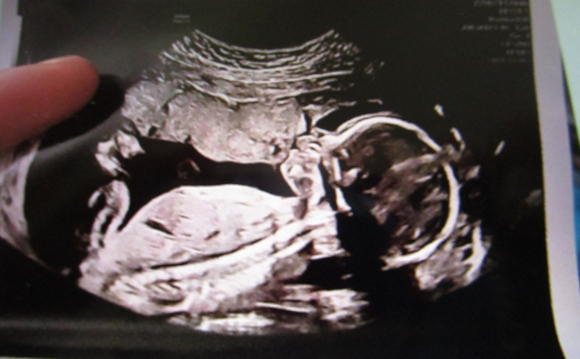

And much of our work continues to be helping moms who chose LIFE! Enjoy these photos.

And contrary to the pro-abortion lie—pro-lifers help mothers, months, even years after the saved babies are BORN! Angelo above was born 11 years ago—and we still help his mom!